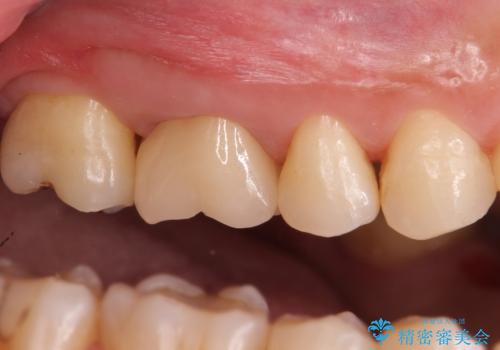

セラミックは劣化で変色することがありません。

表面も滑沢で汚れが付着しにくく、適合の良いセラミッククラウンは治療後の虫歯リスクを抑えてくれます。